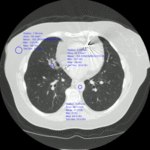

Acute aspiration

A. Portable upright chest x-ray before aspiration; B. Chest x-ray 1 hour after aspiration, showing bilateral diffuse alveolar infiltrates, worse at the bases on the right side

From the collection of Dr Henri Colt